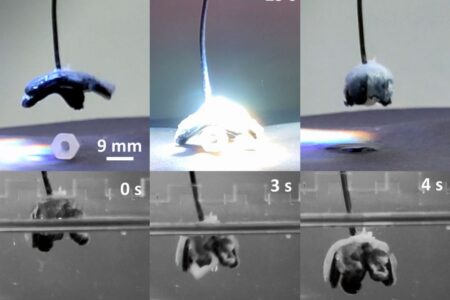

Biokompatible Mikrofasern als Gerüst für Organe effizient hergestellt

Wer Haut und Organe per Tissue Engineering herstellen möchte, benötigt körperverträgliche Mikrofasern als Gerüst. Daran forscht ein Team der TU Graz.